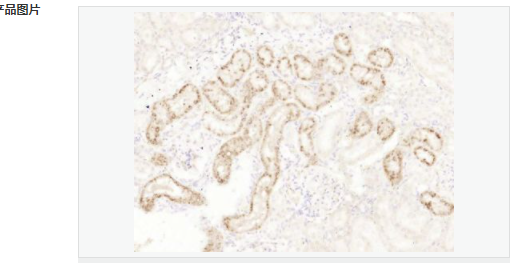

| 產(chǎn)品應(yīng)用 | ELISA=1:5000-10000 IHC-P=1:100-500 IHC-F=1:100-500 ICC=1:100-500 IF=1:100-500 (石蠟切片需做抗原修復(fù)) not yet tested in other applications. optimal dilutions/concentrations should be determined by the end user. |